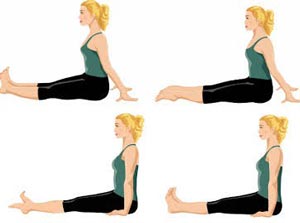

تمرینات کششی رایج برای تسکین، درمان، و یا جلوگیری از درد کف پا عبارتاند از:

- کشش فاشیای کف پا

- خم کردن پا

- کشش و غلتاندن کف پا